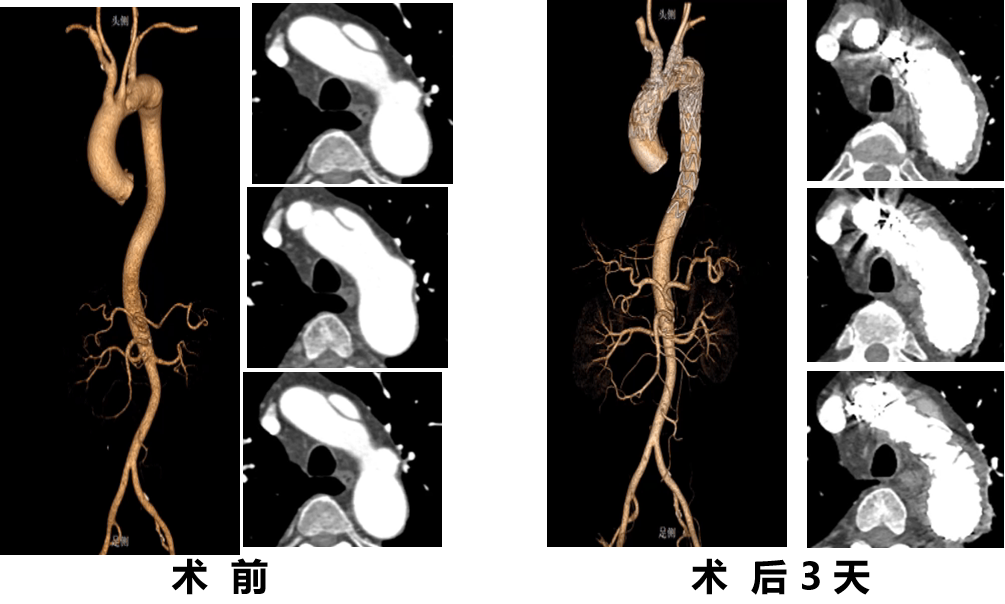

★ 病例2:模块内嵌分支胸主动脉覆膜支架系统

术前

术后